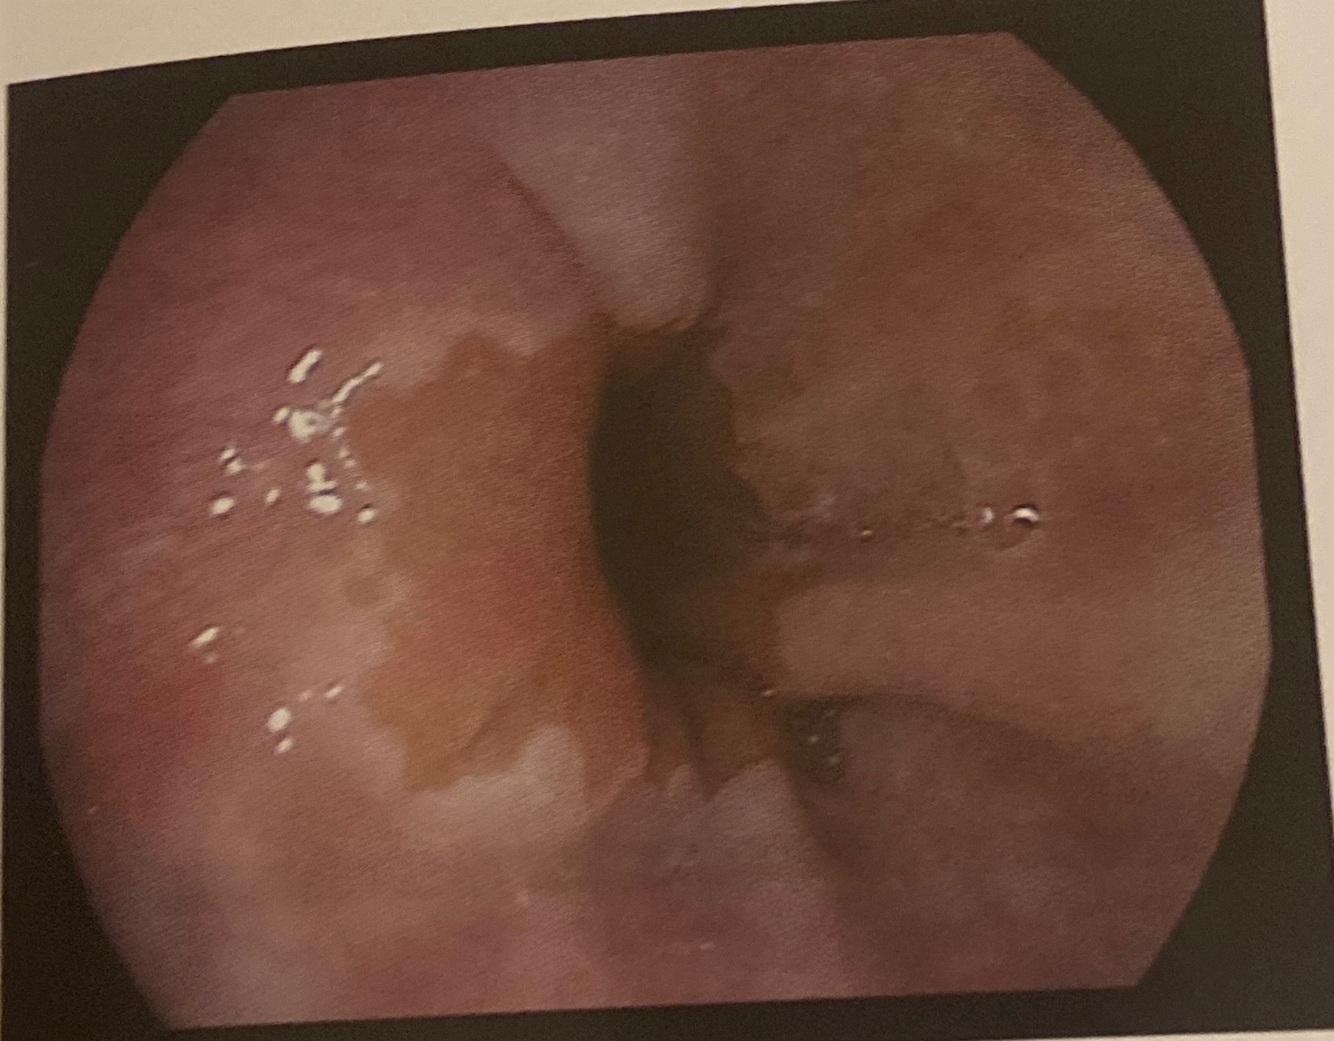

17

Endoscopia em megaesôfago

Aspectos endoscópicos do megaesôfago: dilatação, mucosa espessada de estase, estase alimentar